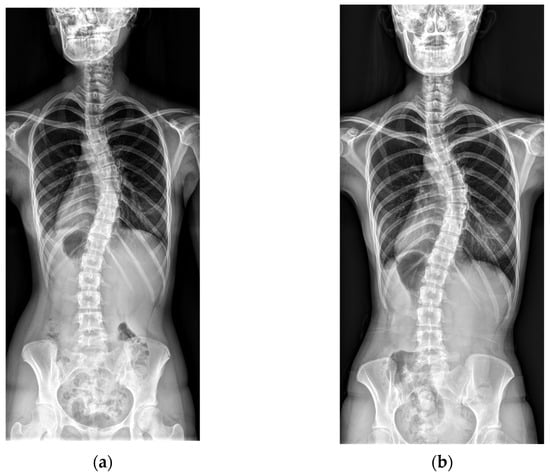

Representative cases from the no-progression and progression groups are shown in Figure 1 and Figure 2.

Figure 2. An example of curve progression. (a) A baseline radiograph of a 14-year-old female patient with Risser stage IV and a Cobb angle of 44°. (b) A final radiograph at age 26, showing Risser stage V and a Cobb angle of 62°.